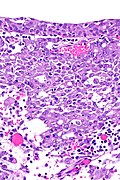

Renal medullary carcinoma (right of image), reactive urothelium and sickled red blood cells. H&E stain. (WC/Nephron) | |

| LM | variable architecture (reticular - resembling a net, adenoid cystic carcinoma-like, yolk sac tumour-like), desmoplastic stroma (usu. prominent), drepanocytes (sickled red blood cells) |

- Variable architecture:

- Reticular (resembling a net) - classic.

- Adenoid cystic carcinoma-like appearance:

- Cystic spaces.

- Yolk sac-like.

- Tubular.

- Desmoplastic stroma - prominent.

- Inflammation:

- Lymphocytes.

- Neutrophils - margination in vessels.

- +/-Drepanocytes (sickled red blood cells) - especially among extravascular red blood cells.